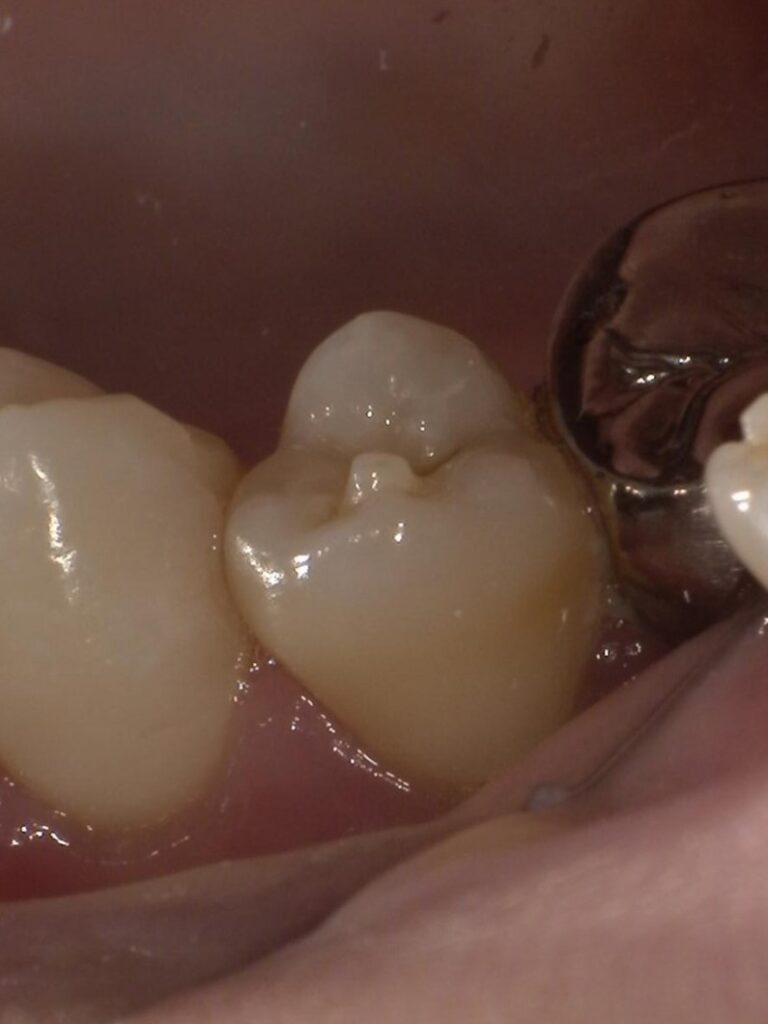

「中心結節」とは、主に下の小臼歯(前から5番目、または4番目の歯)の噛み合わせの面にできる、小さな突起のことです。これは一種の形態異常ですが、日本人には比較的多く見られ(出現率は数%と言われています)、決して稀なものではありません。

最大の問題点は、「突起の内部まで神経(歯髄)が入り込んでいることが多い」という点です。

生えたての永久歯にあるこの突起は、細くて折れやすく、食事の際の衝撃や歯ぎしりなどで、容易に折れてしまうことがあります。突起がポキッと折れると、そこから中の神経が露出(露髄)してしまいます。